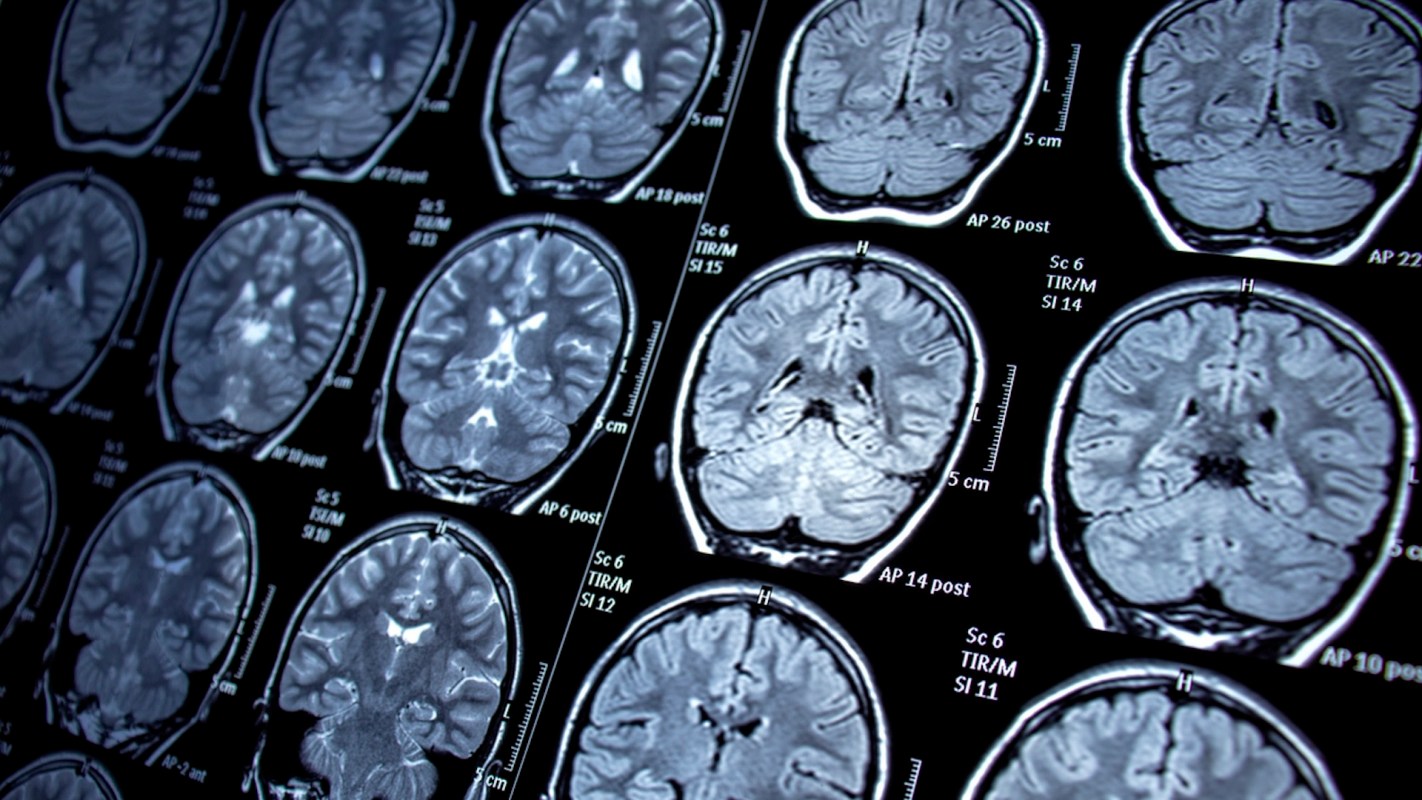

A new study has linked exposure to per- and polyfluoroalkyl substances, also known as "forever chemicals," to some concerning changes in the brain.

They found that PFAS influenced the activity of more than 700 genes in brain cells, 11 of which were consistently impacted.

One notable discovery, per the About Lawsuits summary, was that PFAS reduced the activity of a gene critical to brain cell survival while increasing the activity of another gene associated with brain cell death, thereby contributing to neurotoxicity, or damage to the brain caused by exposure to toxic substances.